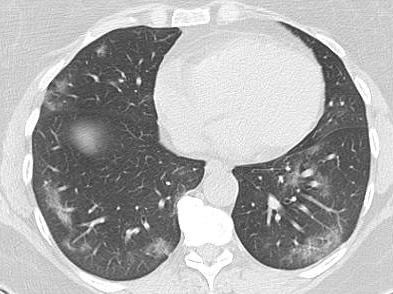

In order to make our models more transparent and provide detailed visual analysis, we present the Grad-CAM localization maps obtained by different models. We consider CT images with COVID-19 abnormalities from the test set of each dataset and highlight the important regions considered for the prediction. For the SARS-CoV-2 dataset we use the Inception V3 model. Figure 13 shows the original CT images and their localization maps. Our model is capable to detect regions that show abnormalities in the CT scans.

A wide variety of typical and atypical CT abnormalities have been reported for COVID-19 patients in various studies [58, 59]. So, we tested our models on external CT images extracted from these two publications as they feature typical findings of COVID-19 pneumonia marked by specialists. In order to make sure that not any of the extracted images are unintentionally included in our datasets, specifically the COVID19-CT dataset, we use the model trained on the SARS-CoV-2 dataset. First, the InceptionV3 model is employed to classify the extracted CT images. The model is able to correctly classify the given CT images as COVID-19. Second, in order to interpret the model’s generalization capabilities, we apply the Grad-CAM technique to visualize the regions of abnormalities that are considered. By assessing the different CT images in Figure 15, we can see that the model accurately localizes the disease-related regions. Even more interesting is the fact that the model ignores any specific marks in the images like letters and only localizes the COVID-19 related regions. These visual explanations show the success of our models to learn relevant, generic visual features related to COVID-19 and are capable to correctly classify CT images outside the datasets on which they are trained.